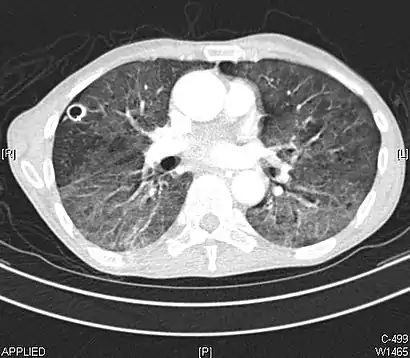

- CT showing diffuse ground-glass opacities in periphery of both lungs in patient with COVID-19.

Ground-glass opacity is among the most common imaging findings in patients with confirmed COVID-19.[16][17] One systematic review found that among patients with COVID-19 and abnormal lung findings on CT, greater than 80% had GGOs, with greater than 50% having mixed GGOs and consolidation.[16] GGOs with mixed consolidation has most often been found in elderly populations.[18] Several studies have described a pattern among initial, intermediate, and hospital discharge imaging findings in the disease course of COVID-19. Most commonly, initial CT imaging reveals bilateral GGOs at the periphery of the lungs. During initial stages, this is most often found in the lower lobes, although involvement of the upper lobes and right middle lobe has also been reported early in the disease course.[16][18] This is in contrast to the two similar coronaviruses, SARS and MERS, which more commonly involve only one lung on initial imaging.[19][20] As the COVID-19 infection progresses, GGOs typically become more diffuse and often progress to consolidation.[11][18] This is sometimes accompanied by the development of a crazy paving pattern and interlobular septal thickening.[18] In many cases the most severe pulmonary CT abnormalities occurred within 2 weeks after symptoms began.[17] At this point, many individuals begin showing resolution of consolidation and GGOs as symptoms improve. However, some patients have worsening symptoms and imaging findings, with further increase in septal thickening, GGOs, and consolidation. These patients may develop lung "white-out" with progression to acute respiratory distress syndrome (ARDS) requiring treatment escalation.[17][21]

Preliminary reports have shown many patients have residual GGOs at time of discharge from the hospital. Due to the novelty of COVID-19, large studies investigating the long-term pulmonary CT changes have yet to be completed. However, long-term pulmonary changes have been seen in patients after recovery from SARS and MERS, suggesting the possibility of similar long-term complications in patients who have recovered from acute COVID-19 infection.[22]